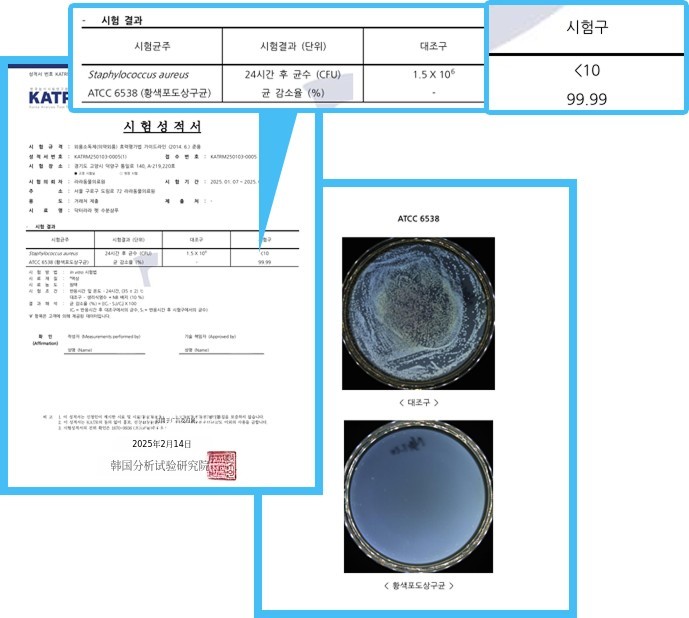

Dr.Lala宠物保湿洗发水的抑菌能力如何?

✅金黄色葡萄球菌/大肠杆菌 99.99%!

- 金黄色葡萄球菌认证书 -

- 金黄色葡萄球菌认证书 - - 大肠杆菌认证书 -